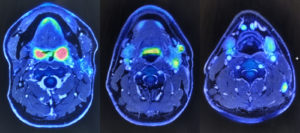

そして年も明けて1月12日、ちょうど予定されていたCT検査があった。検査の後、定期検診で頭頸部外科の担当医の診察で、その像を見てみると、再発の疑い濃厚、と。断面図を見ると、素人目でもわかるほど、半年前に受けた時の像よりも、該当箇所が大きくなっている。リンパ節痕もそうだし、加えて、切除した左扁桃腺の箇所も。深部なので、左扁桃腺は、表面を見たり触診では分からない。そこで急遽、3日後にPET-MRI検査を受けることになった。この経過はパートナーじょにおにももちろん話し、PET-MRI検査後の診察と治療方針を聞くにあたっては、じょにおも同席した。ちなみに我々は、初回の入院手術に先立ち、パートナーシップに関する公正証書を取り交わしており、互いの看護権者になっている。

結果は再発。MRIの画像では、CTで明らかになった2箇所にくわえ、左顎の下のリンパ節(これは前回切除の必要なく残っている)もだと。手術ではかなり大掛かりで皮膚移植の必要などもあり、外貌の大きな変化も免れないので、今回は放射線治療と抗がん剤投与を勧める、とのことだった。